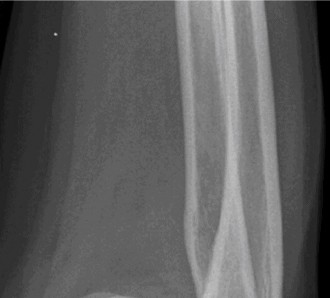

It should be noted that reverse total shoulder arthroplasty is also the procedure of choice in patients with cuff-tear arthropathy (aka rotator cuff arthropathy). Characteristics of cuff-tear arthropathy include superior migration of the humerus due to a massive rotator cuff tear, glenohumeral joint destruction, subchondral osteoporosis, and humeral head collapse (see Fig. 2–17). A reverse total shoulder

Figure 2–17_X-rays of a patient showing evidence of cuff tear arthropathy. The humerus is migrated superiorly, the glenohumeral joint is destroyed, there is subchondral osteoporosis, and the humeral head is collapsed. (From Ecklund KJ, Lee TQ, Tibone J, Gupta R. Rotator cuff tear arthropathy. _J Am Acad Orthop Surg. 2007;15(6):340–349.)